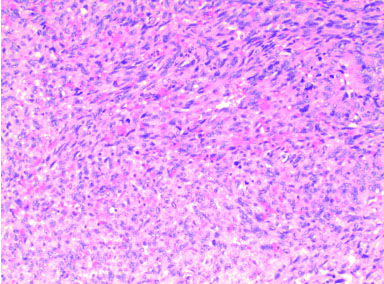

In order to obtain a reliable histologic diagnosis, Mezi et al. [3] recommended a FNAC before surgery. Fine-needle aspiration cytology is widely used in the preoperative adjunctive diagnosis of head and neck tumors, but its diagnostic value for salivary gland tumors is controversial. It has been shown that the ability of FNA to differentiate between benign lesions and malignant tumors for all samples is 83%, for benign tumors 89%, and for malignant tumors 59% [10]. Therefore, FNA is more accurate in the diagnosis of benign parotid tumors. The accuracy of FNA depends on the quality of the sample material and the pathologist’s experience in evaluating it [11]. In this case, the result was false negative, with more inflammatory cell infiltration and multinucleated cell aggregates seen in the perforated tissue, and small foci of moderate anisotropic epithelial hyperplasia (Figure 3). False negatives may be the result of the needle localizing outside the target cells and failing to aspirate tissue from the lesion, necrosis within the tumor, hemorrhage, penetration into areas of cystic degeneration, or poor quality push slides [11],[12]. It can be highly helpful to the operator in developing a treatment plan as a first line of defense for the diagnosis of parotid malignancy, but some surgeons are less confident due to its relatively low sensitivity, false-negative, and false-positive outcomes [13],[14]. While intraoperative frozen sections are extremely reliable for detecting PPSCC, they are also crucial for excluding malignancy when the results of an FNAB are in doubt [15]. A basis for a clear intraoperative treatment plan is provided. Additionally, as PPSCC typically lacks any mucous cells, the application of specific stains (such as PAS reaction, Astra, or Alzian blue) is a useful supplementary diagnostic approach to distinguish MEC [8],[16].

Figure 3: More inflammatory cell infiltration and multinucleated cell aggregates were seen in the tissues, as well as small foci of moderate anisotropic epithelial hyperplasia.